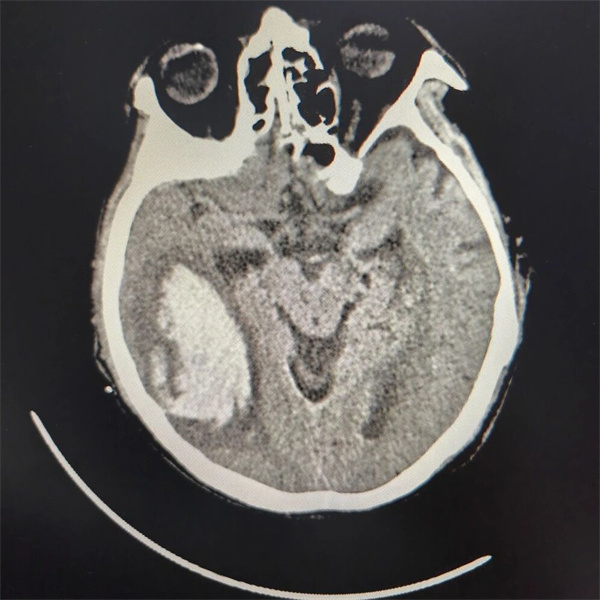

手术灯亮起的瞬间,一场与死神的“近身搏斗”正式展开。老年患者的脑组织本就脆弱如绵,加之血肿长期压迫导致解剖结构移位,精准定位血肿腔成为首要难题。神经外科团队成员各司其职,吸除血肿、止血、保护功能区,每一个动作都沉稳有序。经过3小时的紧张奋战,颅内83.7ml血肿被彻底清除,颞肌下减压术为肿胀的脑组织“松了绑”,颅内压监测电极成功植入,实时数据显示颅内压从术前的35mmHg降至15mmHg以下——这一安全数值的出现,意味着生命体征已逐步平稳。当老人的自主呼吸开始逐渐恢复时,手术室里响起了压抑许久的掌声。这掌声里,有对生命的敬畏,更有对团队协作的致敬。

▲ 术后患者头颅CT影像